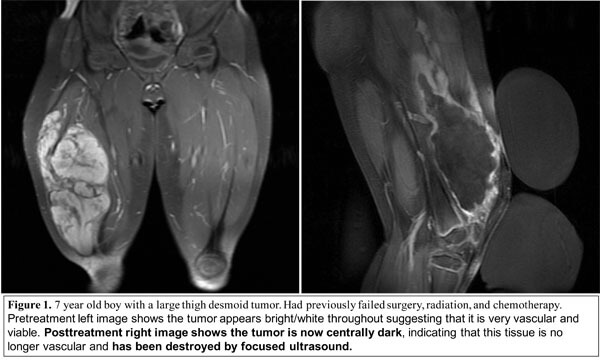

Because of the similarities between desmoid tumors and uterine fibroids, HIFU was pursued as a treatment for patients with desmoid tumors. HIFU is not FDA-approved for this indication, which means that the government does not believe there is enough evidence to definitively judge its safety or efficacy. However, in several early clinical studies, HIFU has shown promise as a treatment option. In the largest study to date of 15 patients with desmoid tumors (25 total treatments), total tumor volume decreased 63% and pain improved from approximately 6 on a 1-10 scale to 1.3, on average.